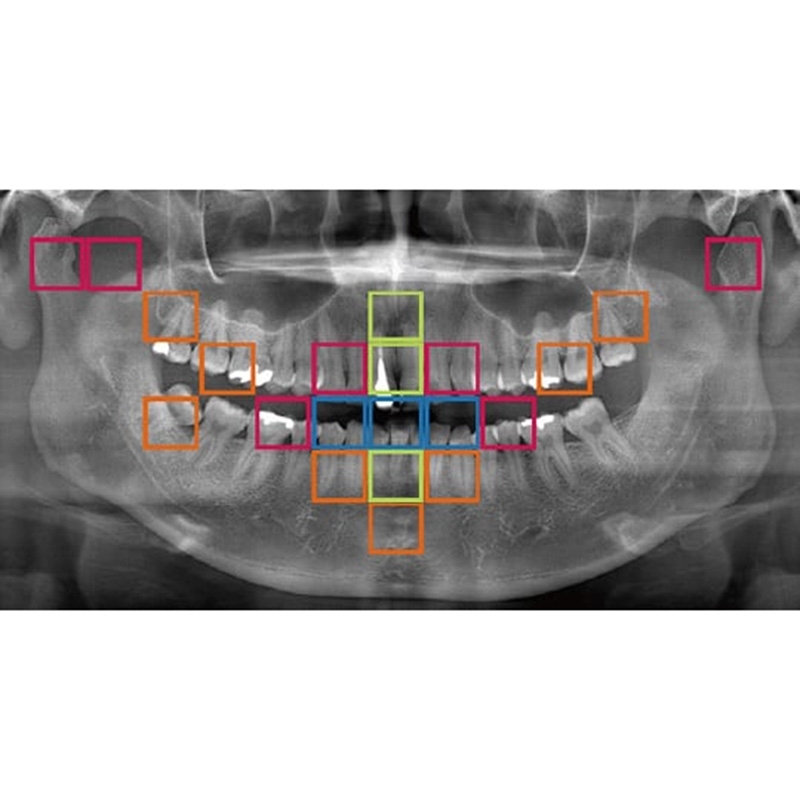

Information / DemoPanorama 2D

Veraview (IC5 HD) Spezifikationen

High-Speed-Modus - 5,5 Sek./192 µm

High-Definition Modus - 10 Sek./96 µm - Lichtvisiere: